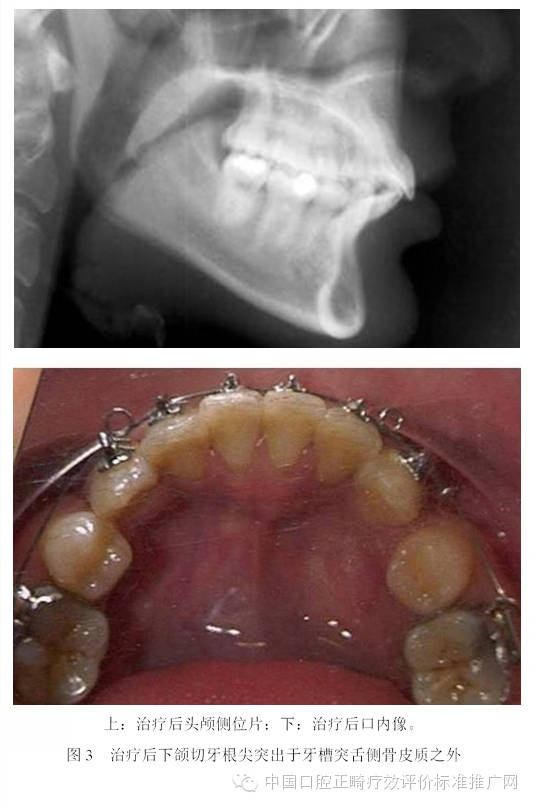

為了避免支抗的丟失,正畸醫(yī)師終于發(fā)現(xiàn)了最強的支抗裝置---金屬種植釘支抗。在用支抗磨牙拉前突的切牙時,切牙牙根在接觸腭側骨皮質后移動的阻力會非常大,于是支抗磨牙會前移而最終關閉間隙;但當改用種植釘支抗拉前牙時,由于種植釘是絕對支抗,在矯治力作用下幾乎不動[6],因此當切牙牙根與腭側骨皮質接觸后,種植釘仍然不會作任何讓步,那么進一步對抗的結果會怎么樣?理想的結果是腭側骨皮質的牙根一側發(fā)生骨吸收,而舌側骨板發(fā)生骨沉積,牙齒帶著牙槽骨一起向腭側移動。問題是骨吸收與骨沉積的數(shù)量相等嗎?速度一致嗎?為了回答這個問題,筆者[7]10年前作過一個上頜切牙內收對其前后方牙槽骨改建的探索性研究。該研究選擇55例平均年齡為13.3歲的青少年錯合患者為研究對象,采用拔除上下頜第一前磨牙進行矯治,平均保持時間為3年。通過測量上切牙阻力中心前方及后方牙槽骨在治療前、治療后及保持后的骨量變化,以及牙槽突總厚度在上述3個時間點的變化,結果發(fā)現(xiàn):上切牙阻力中心在治療后向腭側平均移動了1.8mm (P<0.001);與阻力中心水平的唇側牙槽骨厚度增加了0.2mm (P<0.01),腭側牙槽骨厚度減小了0.8mm (P<0.001);隨訪期上切牙阻力中心向唇向復發(fā)了0.8mm (P<0.01),與阻力中心水平的唇側牙槽骨厚度相應減小了0.2mm (P<0.05),但腭側牙槽骨厚度卻并沒有明顯的增加;與上切牙阻力中心水平的牙槽突總厚度基本保持在治療后的水平。由此可見,在牙齒移動的過程中,牙槽骨的生物學改建是以骨吸收為主,骨增生十分有限,即使是保持3年以后,骨增生的量也未達到其吸收的量。雖然這只是個初淺的臨床研究,尚有待基礎研究去證實,但它卻部分解釋了正畸臨床上在對骨性錯合患者進行牙代償性矯治時,會出現(xiàn)牙槽骨吸收、裂隙、穿孔,牙齦萎縮或部分根尖移出牙槽骨的現(xiàn)象[8-13]。圖3為1例成人患者在用牙代償性治療方法減少重度深覆蓋深覆合時出現(xiàn)切牙根尖從舌側移出牙槽骨的X線影像;圖4為1例采用種植釘支抗大量內收上下頜前牙的患者,治療后牙根移出至牙槽突之外的錐形束CT影像。